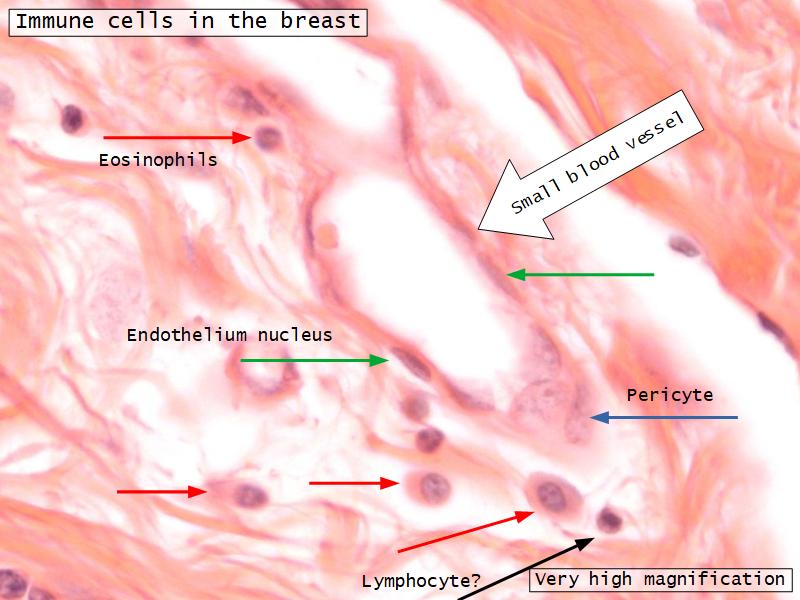

Mammary gland

Write short notes describing the structure of the mammary gland.

Resting gland

- Connective tissue dominate

- More adipose tissue

- Glandular tissue reduced

Active gland

- Terminal ducts expand

- Forms alveoli

- Connective tissue reduced

- Adipose tissue reduced

- Glandular tissue dominate

Structures

List the structures and cells found in the mammary gland.

Structures

- Lactiferous sinuses

- Stratified squamous near opening on skin

- Stratified cuboidal other parts

- Lactiferous ducts

- Stratified cuboidal

- Myoepithelial cells

- Underlie lactiferous ducts in most areas

- Basal lamina

- Separate epithelial components from stroma

Active gland

- Much larger than resting phase

- Terminal ducts proliferate to form alveoli

- Alveoli

- Surrounded by incomplete myoepithelial cells

Alveolar cells

- Apocrine secretion

- Active state

- Resting state